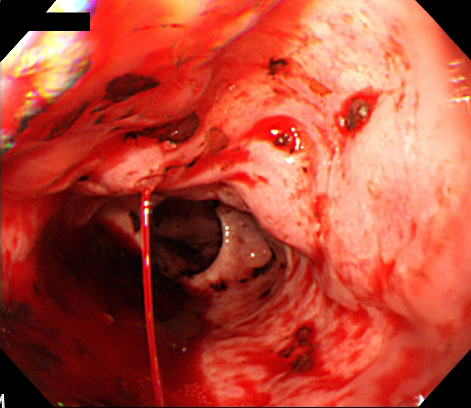

食道静脈瘤出血の内視鏡所見

下部食道から噴出性出血を認める。